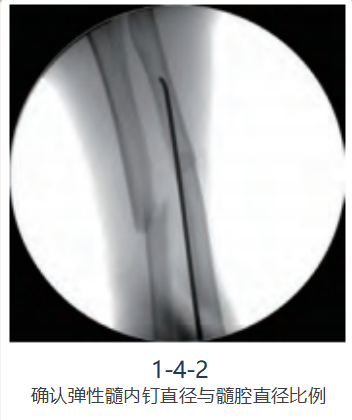

尺、桡骨通过骨间膜形成一个整体, 在前臂只需在尺、桡骨各行一枚弹性髓内钉固定即可。 测量本例髓腔最狭窄处直径为4.0mm,术中选用弹性 髓内钉直径为2.5mm。将选择好的弹性髓内钉放置于骨折平面,于“C”型臂X线机下透视,确认直径是否适宜(图1-4-2)。